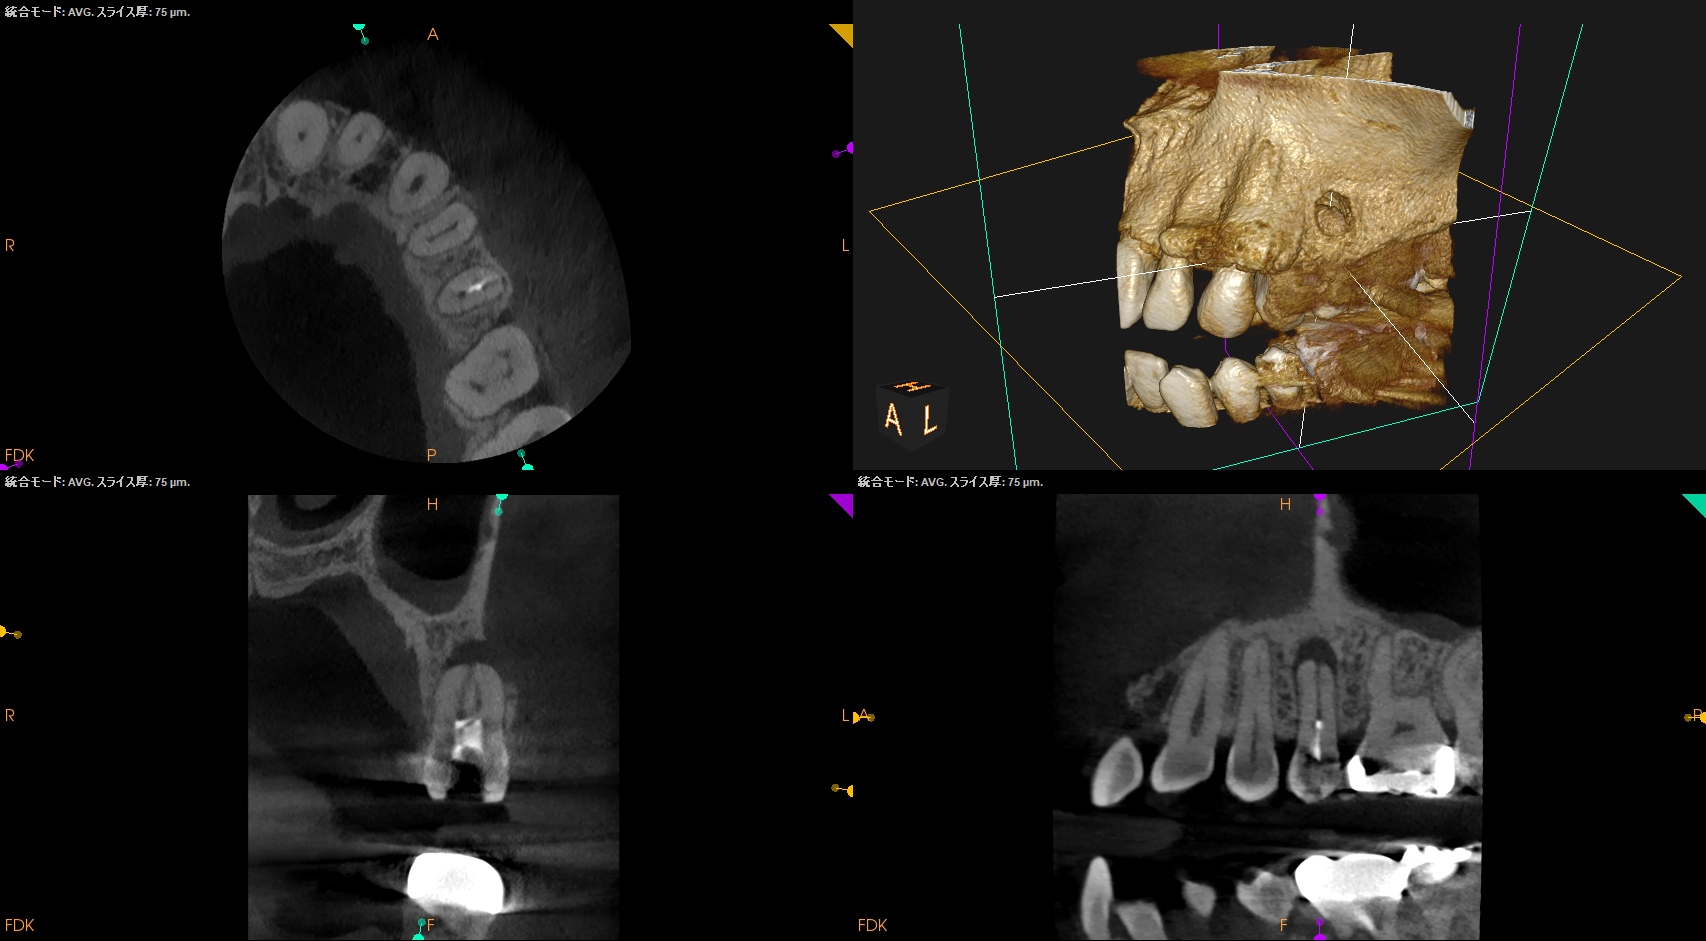

#13 RCT(2025.2.4)

合流地点を確認し以下のように根管形成して

術後にPA, CBCTを撮影した。

ここから1年が経過した。

#13 RCT 1yr recall(2026.2.26)

1年前と比較した。

根尖病変は大きく縮小し、臨床症状(圧痛)も消失したのでかかりつけ医の先生には最終補綴を依頼した。

次回はさらに1年後である。